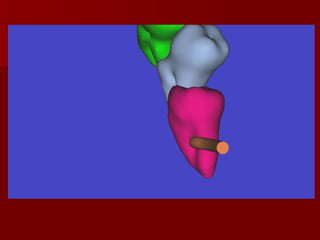

Imaging of Lingual Nerve Injuries CT

Imaging of LingualNerve Injuries CT